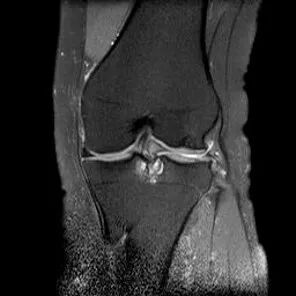

桶柄状撕裂MRI表现

1、宽度减小,在通过半月板体部的冠状面上蝶形消失,同时可见内移的半月板位于髁间窝、交叉韧带旁2、矢状面示残余的前角或后角变小或截断3、半月板前(后)角增宽或双半月板前(后)角征4、双前交叉韧带或双后交叉韧带征

桶柄状撕裂:半月板后角增宽